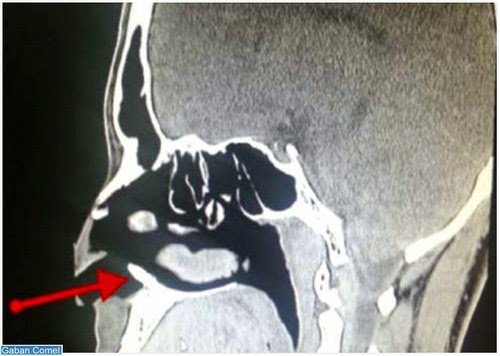

Lelaki berusia 22 tahun yang tidak tahan mengalami masalah hidung berdarah sekurang-kurangnya sekali setiap bulan sejak tiga tahun lalu terkejut apabila dimaklumkan gigi sebesar satu sentimeter ditemui di dalam lubang hidungnya yang disahkan doktor gigi adalah gigi tambahan.

Gigi itu mengakibatkan pendarahan setiap kali lelaki terbabit menggosok hidungnya.

Masalah hidung berdarah selesai selepas gigi itu dikeluarkan dalam satu pembedahan kecil.